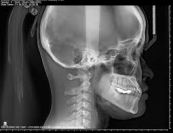

Chụp x quang mặt giúp tìm gãy xương, khối u, dị vật, nhiễm trùng và tăng trưởng bất thường hoặc thay đổi cấu trúc hoặc kích thước xương. Để hiểu rõ hơn về thủ thuật này, mời các bạn tham khảo bài viết dưới đây!